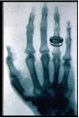

По этой причине Рентген не знал о сделанных до него открытиях и открыл лучи, названные впоследствие его именем, независимо - при наблюдении флюоресценции, возникающей при работе катодолучевой трубки. Рентген занимался Х-лучами немногим более года (с 8 ноября 1895 года по март 1897 года) и опубликовал о них всего три сравнительно небольших статьи, но в них было дано столь исчерпывающее описание новых лучей, что сотни работ его последователей, опубликованных затем на протяжении 12 лет, не могли ни прибавить, ни изменить ничего существенного. Рентген, потерявший интерес к Х-лучам, говорил своим коллегам: "Я уже всё написал, не тратьте зря время". Свой вклад в известность Рентгена внесла также знаменитая фотография руки его жены, которую он опубликовал в своей статье (см. изображение справа). Подобная слава принесла Рентгену в 1901 году первую Нобелевскую премию по физике, причём нобелевский комитет подчёркивал практическую важность его открытия. В 1896 году впервые было употреблено название "рентгеновские лучи". В некоторых странах осталось старое название - X-лучи. В России лучи стали называть "рентгеновскими" с подачи ученика В.К. Рентгена - Абрама Фёдоровича Иоффе.

(Рентгеновская фотография (рентгенограмма) руки своей жены, сделанная В.К. Рентгеном)